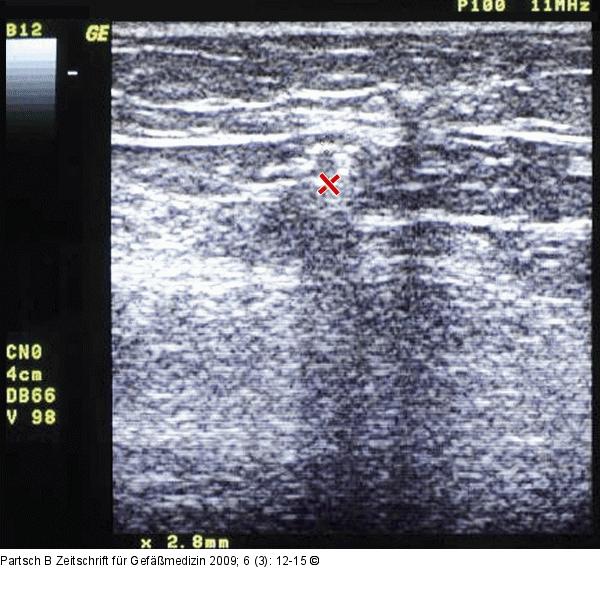

Abbildung 2: Gefäßspasmus

Gefäßspasmus unmittelbar nach der Sklerosierung. |